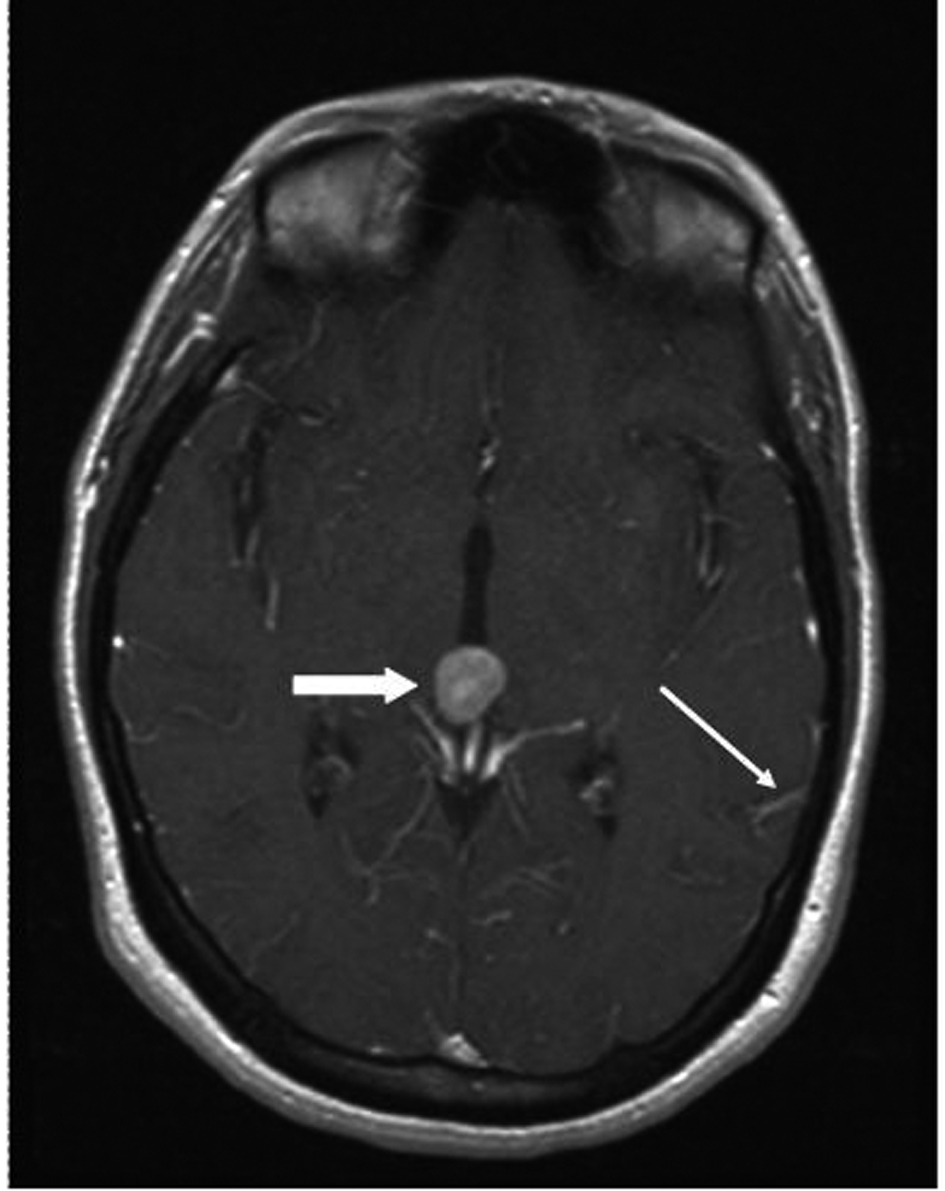

A 33 year old woman presented to the Emergency Department with bifrontal headaches and blurry vision. Her past medical history was significant for Crohn’s disease which required a subtotal colectomy; she was not on any medications at presentation. Physical examination was without additional abnormalities. Magnetic resonance imaging (MRI) of the head revealed an enhancing pineal gland mass (Fig.1 and 2, large arrow) and obstructive hydrocephalus. These findings were concerning for either a primary or secondary brain malignancy. Cerebral spinal fluid (CSF) examination revealed malignant cells from an unknown primary.

![]() Click for large image | Figure 2. MRI brain (transversal) reveals obstructive hydrocephalus caused by an enhancing pineal gland mass (large arrow) and leptomeningeal carcinomatosis (LC) (small arrow). |

The patient was admitted, and a ventriculostomy was placed to treat the hydrocephalus. When the patient stabilized, she received whole brain external beam radiation (3000 cGy in 10 fractions), which resulted in improvement of her vision. MRI defined the pineal gland metastasis and LC as the cause for the hydrocephalus (Fig. 1 and 2, small arrow). The LC progressed despite radiation necessitating the conversion of the ventriculostomy to a ventriculo-peritoneal shunt for the persistent symptomatic hydrocephalus.